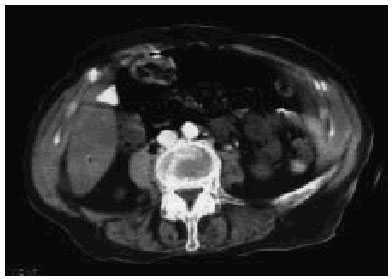

La tomografía axial computarizada (TAC) abdominal puso de manifiesto imágenes de neumatosis intestinal, distensión abdominal, abundante gas en la vena mesentérica y sistema portal (vena porta y esplénica), compatible con isquemia mesentérica grave (figs. 1 y 2).

Fig. 2.